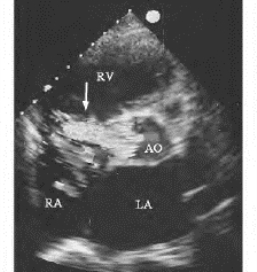

图16-11 无冠状动脉窦瘤破入右房二维与彩色多普勒超声图(见彩图21)

心底短轴,示无冠窦瘤样扩张并破入右房(↓),彩色湍流自无冠窦进入右房